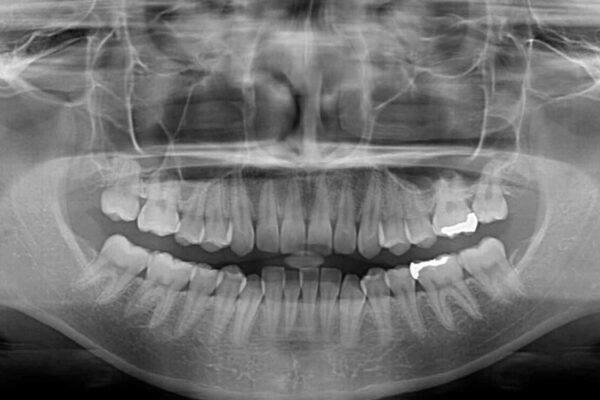

下顎の八重歯を気にして来院された患者様です。

下顎前歯にデコボコが集中していたため、顎間ゴムによる後方移動とIPR(歯と歯の間を削ること)により歯列を整えることとしました。

治療前、下顎前歯のデコボコが集中しており、奥歯の咬み合わせは、上顎に対して下顎が前方位にある状態でした。下顎の歯列を後方へ移動させる治療はインビザラインの得意とするところですので、1年程度で無事に治療を終えることができました。

治療前

• 【モニター】下顎前歯のデコボコをインビザラインできれいに 治療前画像